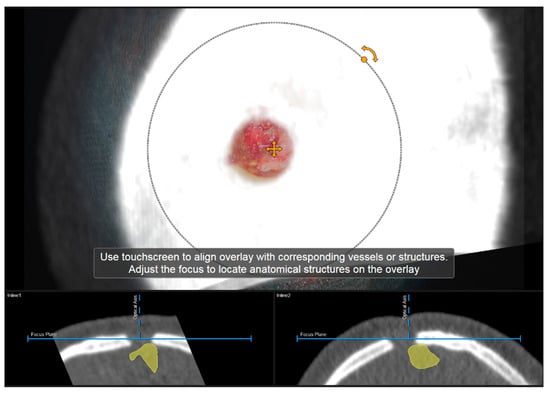

2.4.1. Verification of Navigation Accuracy Using Bony Landmarks

Navigation accuracy can be evaluated using bony landmarks. In cases the iCT registration scan was performed after craniotomy or in cases of recurrent tumors or patients with prior burr-hole surgery (e.g., biopsy) preoperative CT imaging-based navigation accuracy can be evaluated using a CT-based MIP or even outlines of the segmented bone flap. Focusing on the edge of the craniotomy at different areas (if available within the data) or using a burr-hole (see Figure 4) or bony structure of interest to match image content and patient anatomy thereby allows for a visual comparison of image content or segmentation of a patient’s anatomy. By either verifying navigation accuracy or even adjusting the image sets to the recent in-focus plane anatomy of the patient by translating and/or rotating the image data within the recently visualized plane, navigation inaccuracies can be compensated for according to in-plane errors. If corrected, the new registration needs to be verified by the user using the pointer to also account for registration applicability beyond the scope of the in-plane update.

Figure 4.

Evaluation of navigation accuracy using a CT-based MIP projection centered at a burr-hole of a prior biopsy surgery, showing a good match of image and patient data (In parallel view of MIP projection (upper part) and inline views with the recent focus plane (blue line) and the optical axis (dashed blue line) in the bottom part).